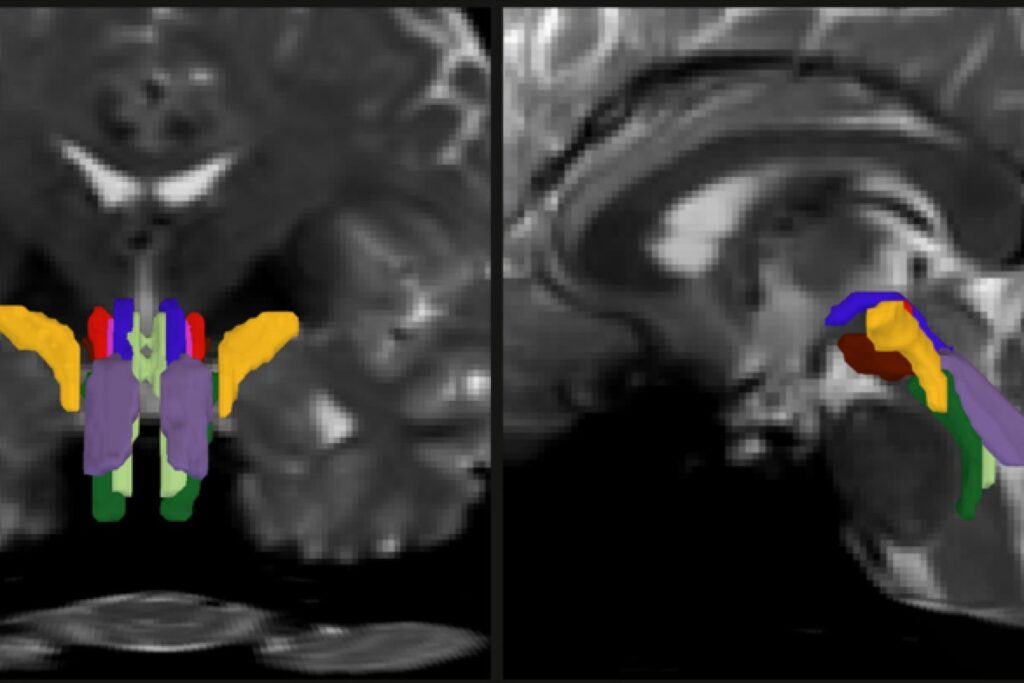

As part of his thesis work to better understand the neural mechanisms that underpin consciousness, Olchanyi wanted to develop an AI algorithm to overcome these obstacles. BSBT works by tracing fiber bundles that plunge into the brainstem from neighboring areas higher in the brain, such as the thalamus and the cerebellum, to produce a “probabilistic fiber map.” An artificial intelligence module called a “convolutional neural network” then combines the map with several channels of imaging information from within the brainstem to distinguish eight individual bundles.

To train the neural network to segment the bundles, Olchanyi “showed” it 30 live diffusion MRI scans from volunteers in the Human Connectome Project (HCP). The scans were manually annotated to teach the neural network how to identify the bundles. Then he validated BSBT by testing its output against “ground truth” dissections of post-mortem human brains where the bundles were well delineated via microscopic inspection or very slow but ultra-high-resolution imaging. After training, BSBT became proficient in automatically identifying the eight distinct fiber bundles in new scans.

Olchanyi, Brown and their co-authors applied BSBT to scores of datasets of diffusion MRI scans from patients with Alzheimer’s, Parkinson’s, MS, and traumatic brain injury (TBI). Patients were compared to controls and sometimes to themselves over time. In the scans, the tool measured bundle volume and “fractional anisotropy,” (FA) which tracks how much water is flowing along the myelinated axons versus how much is diffusing in other directions, a proxy for white matter structural integrity.